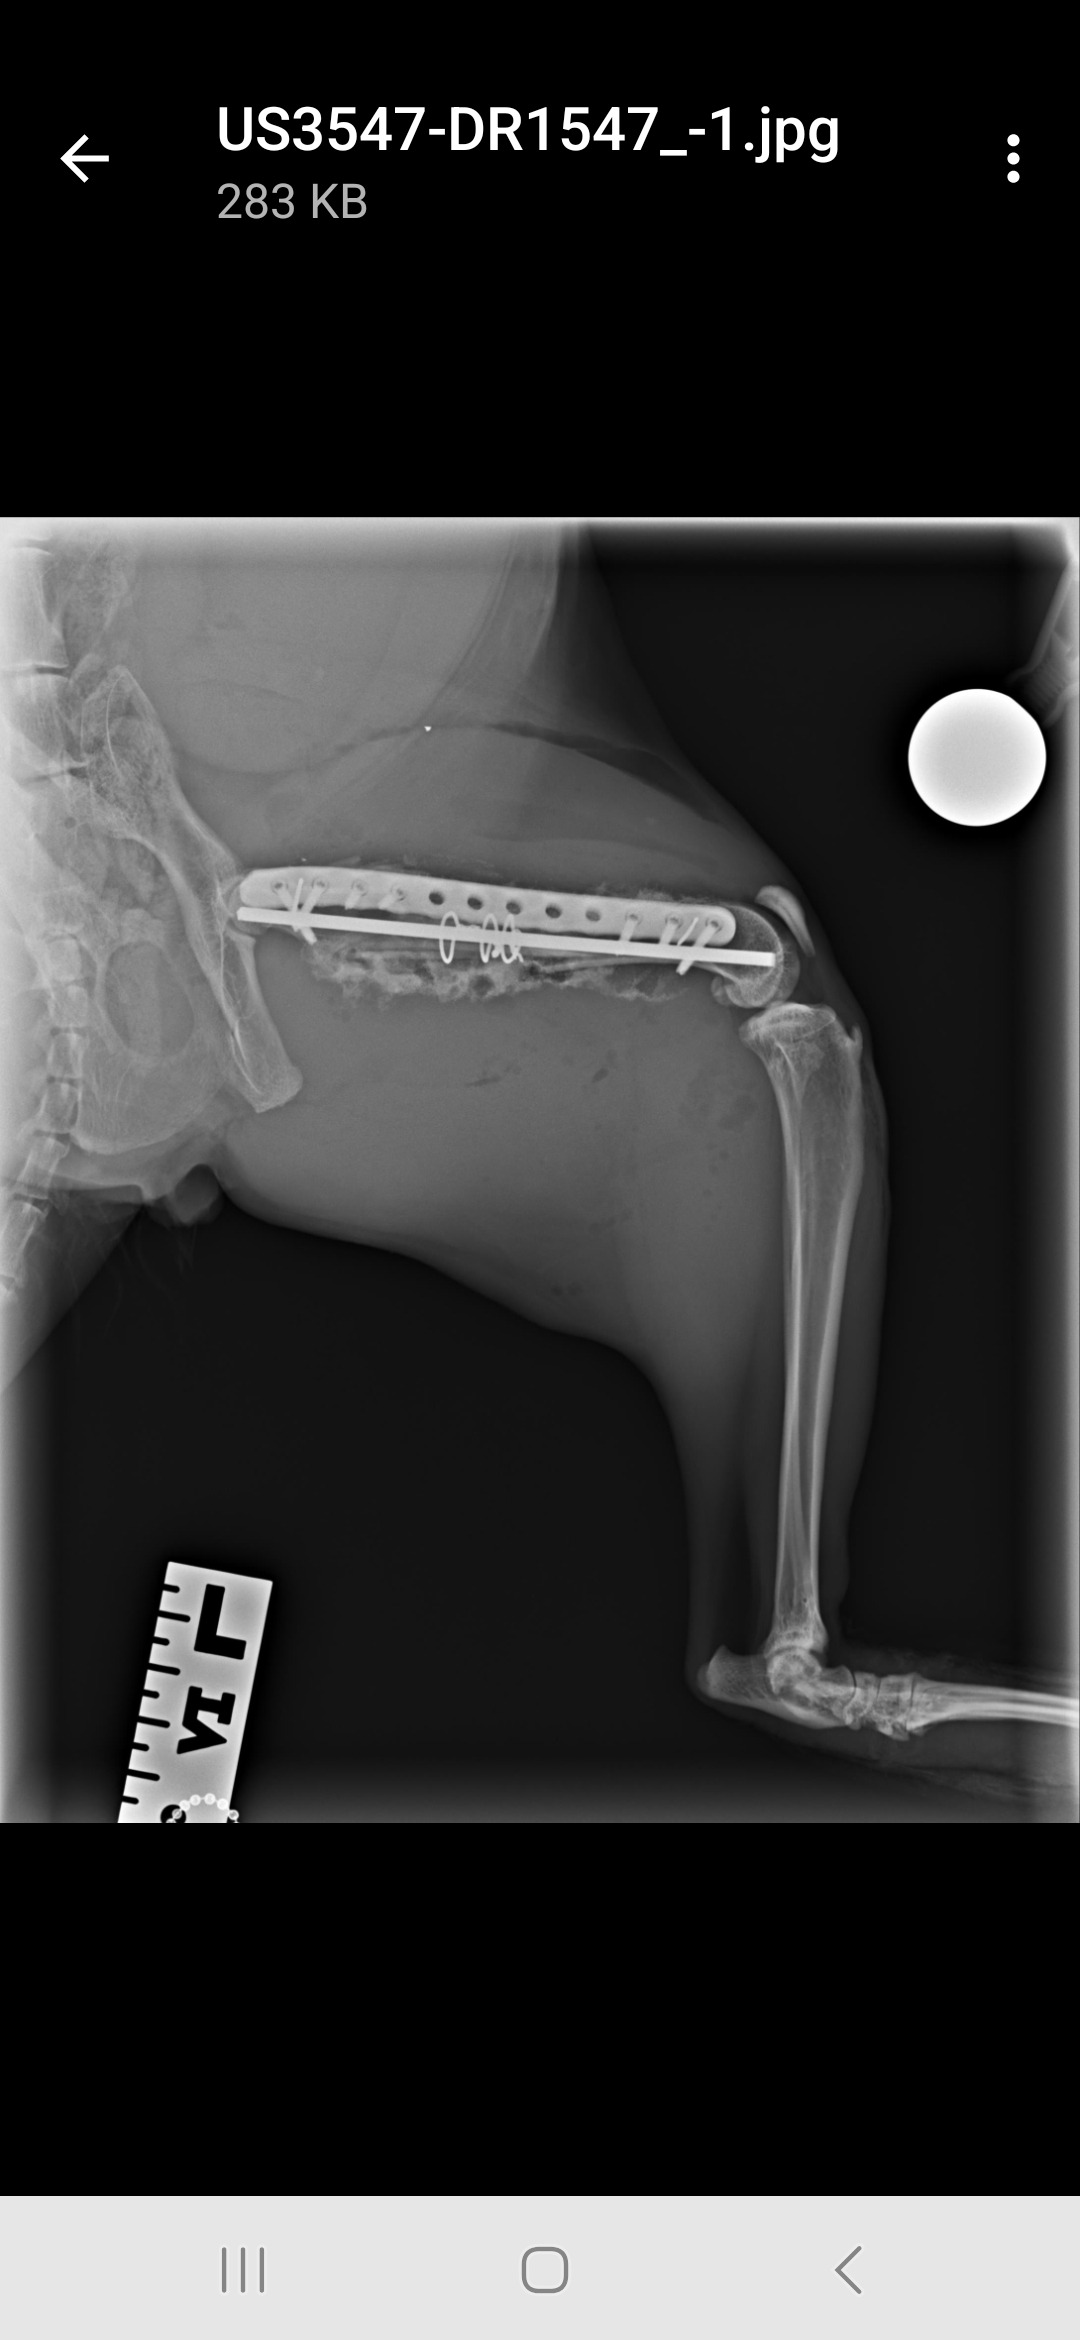

Last week my sweet fluffin-muffin, Teddy Bear, was attacked by the neighborhood bully cat, Snoop Dog. The incident happened on a neighbor’s roof, and during the struggle Teddy fell onto the concrete below, breaking his femur.

The injury was so bad that our vet recommended amputation. They obviously didn’t know who they were talking to. I would never let this senseless act of violence deform my angel. So, even though I’ve been unemployed since February and have zero money to spare, I did what any fur mom would do and found a surgeon to save his leg.

Now Teddy is home and recovering, confined to a cage for the next 5–8 weeks. Grateful to have a leg, and purrleased if you could spare $5–10 to #saveteddysleg